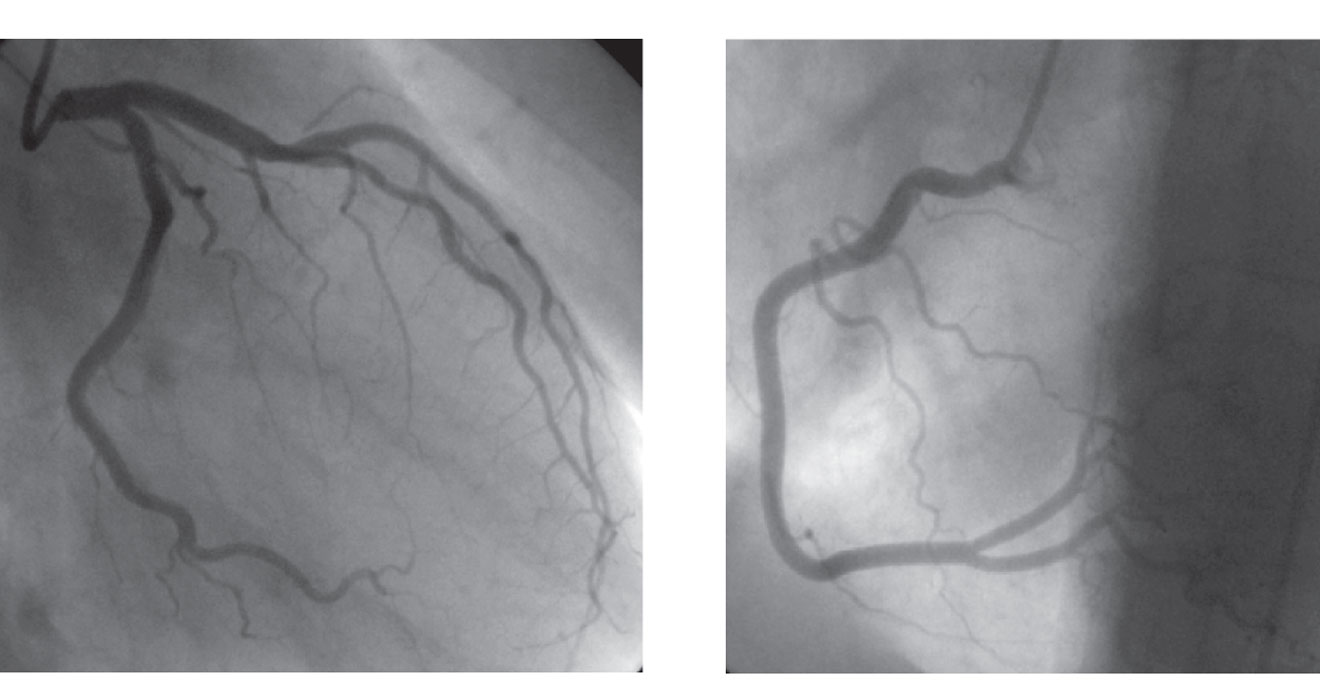

Coronary Angiogram

Specialized procedures to treat challenging coronary artery blockages.